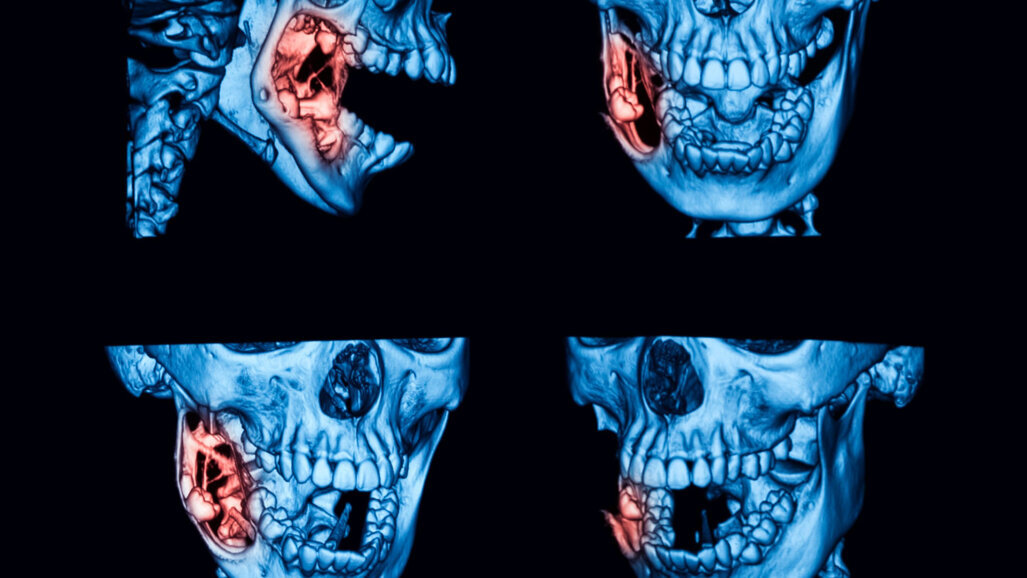

TURKU, Phần Lan: Được cho là phát sinh từ phần còn sót lại của lá răng, nang sừng do răng (OKC) chiếm khoảng 5%–15% tổng số u nang do răng và xuất hiện dưới dạng tổn thương đơn độc hoặc nhiều tổn thương. Chúng thường phát triển nhanh chóng và có tỷ lệ tái phát cao. Nghiên cứu được thực hiện tại Đại học Turku trên dân số Phần Lan đã phát hiện ra rằng bệnh nhân mắc OKC có xu hướng lớn tuổi hơn vào thời điểm chẩn đoán và u nang của họ thường bị viêm hơn so với báo cáo trong tài liệu. Các phát hiện cho thấy sự chậm trễ trong chẩn đoán, vì OKC thường không có triệu chứng và có thể không bị phát hiện cho đến khi các triệu chứng như sưng tấy hoặc nhiễm trùng biểu hiện.

Nghiên cứu hồi cứu đã xem xét dữ liệu trên 174 bệnh nhân được chẩn đoán mắc OKC từ năm 1980 đến năm 2016, nhằm đánh giá các đặc điểm mô bệnh học, tỷ lệ mắc và tái phát của OKC ở tây nam Phần Lan, khu vực chiếm 9% dân số Phần Lan. Nó báo cáo tỷ lệ mắc bệnh là 7,7 trường hợp mỗi năm, phù hợp với sự hiếm có của các báo cáo OKC trong tài liệu.

Ngoài việc phát hiện ra rằng bệnh nhân lớn tuổi hơn, có độ tuổi trung bình là 46, tại thời điểm chẩn đoán so với các báo cáo trước đó, nghiên cứu còn phát hiện ra rằng đáng chú ý 95% OKC bị viêm, con số cao hơn 76% được báo cáo trước đó. . Tỷ lệ viêm nhiễm cao ủng hộ lý thuyết chẩn đoán muộn, sự chậm trễ đã khiến các u nang không được phát hiện phát triển lớn hơn và khiến hệ thống miễn dịch có thời gian kích hoạt tình trạng viêm.

So với 15%–63% trong tài liệu, tỷ lệ tái phát của OKC trong nghiên cứu là 21%. Tỷ lệ cao chưa được hiểu đầy đủ nhưng có thể bị ảnh hưởng bởi các phương pháp điều trị, loại bỏ không đúng cách và sự hiện diện của các nang vệ tinh cực nhỏ, được tìm thấy trong 10% trường hợp, so với 20%–71% trong tài liệu. U nang vệ tinh có liên quan đến tình trạng viêm mãn tính và khả năng tái phát cao hơn và xảy ra phổ biến hơn ở hàm trên. Nghiên cứu cũng quan sát thấy tỷ lệ u nang vệ tinh ở phụ nữ cao hơn một chút. Các tác giả đề nghị nghiên cứu thêm để làm rõ nguyên nhân tái phát và mối quan hệ giữa u nang vệ tinh và tái phát OKC.

Các tác giả cũng cho rằng tuổi bệnh nhân OKC lớn hơn và tỷ lệ mắc u nang viêm cao hơn có thể góp phần vào sự phát triển của u nang vệ tinh. Họ nhấn mạnh rằng điều này nhấn mạnh tầm quan trọng của việc kiểm tra chụp X quang thường xuyên, chẳng hạn như chụp X quang toàn cảnh, đặc biệt là trong thập kỷ thứ hai và thứ ba của cuộc đời, để tạo điều kiện phát hiện sớm và quản lý OKC. Họ cũng khuyến cáo rằng sự xuất hiện của các u nang vệ tinh phải được báo cáo về mặt mô bệnh học, vì chúng có thể biểu thị nguy cơ tái phát OKC tăng lên.